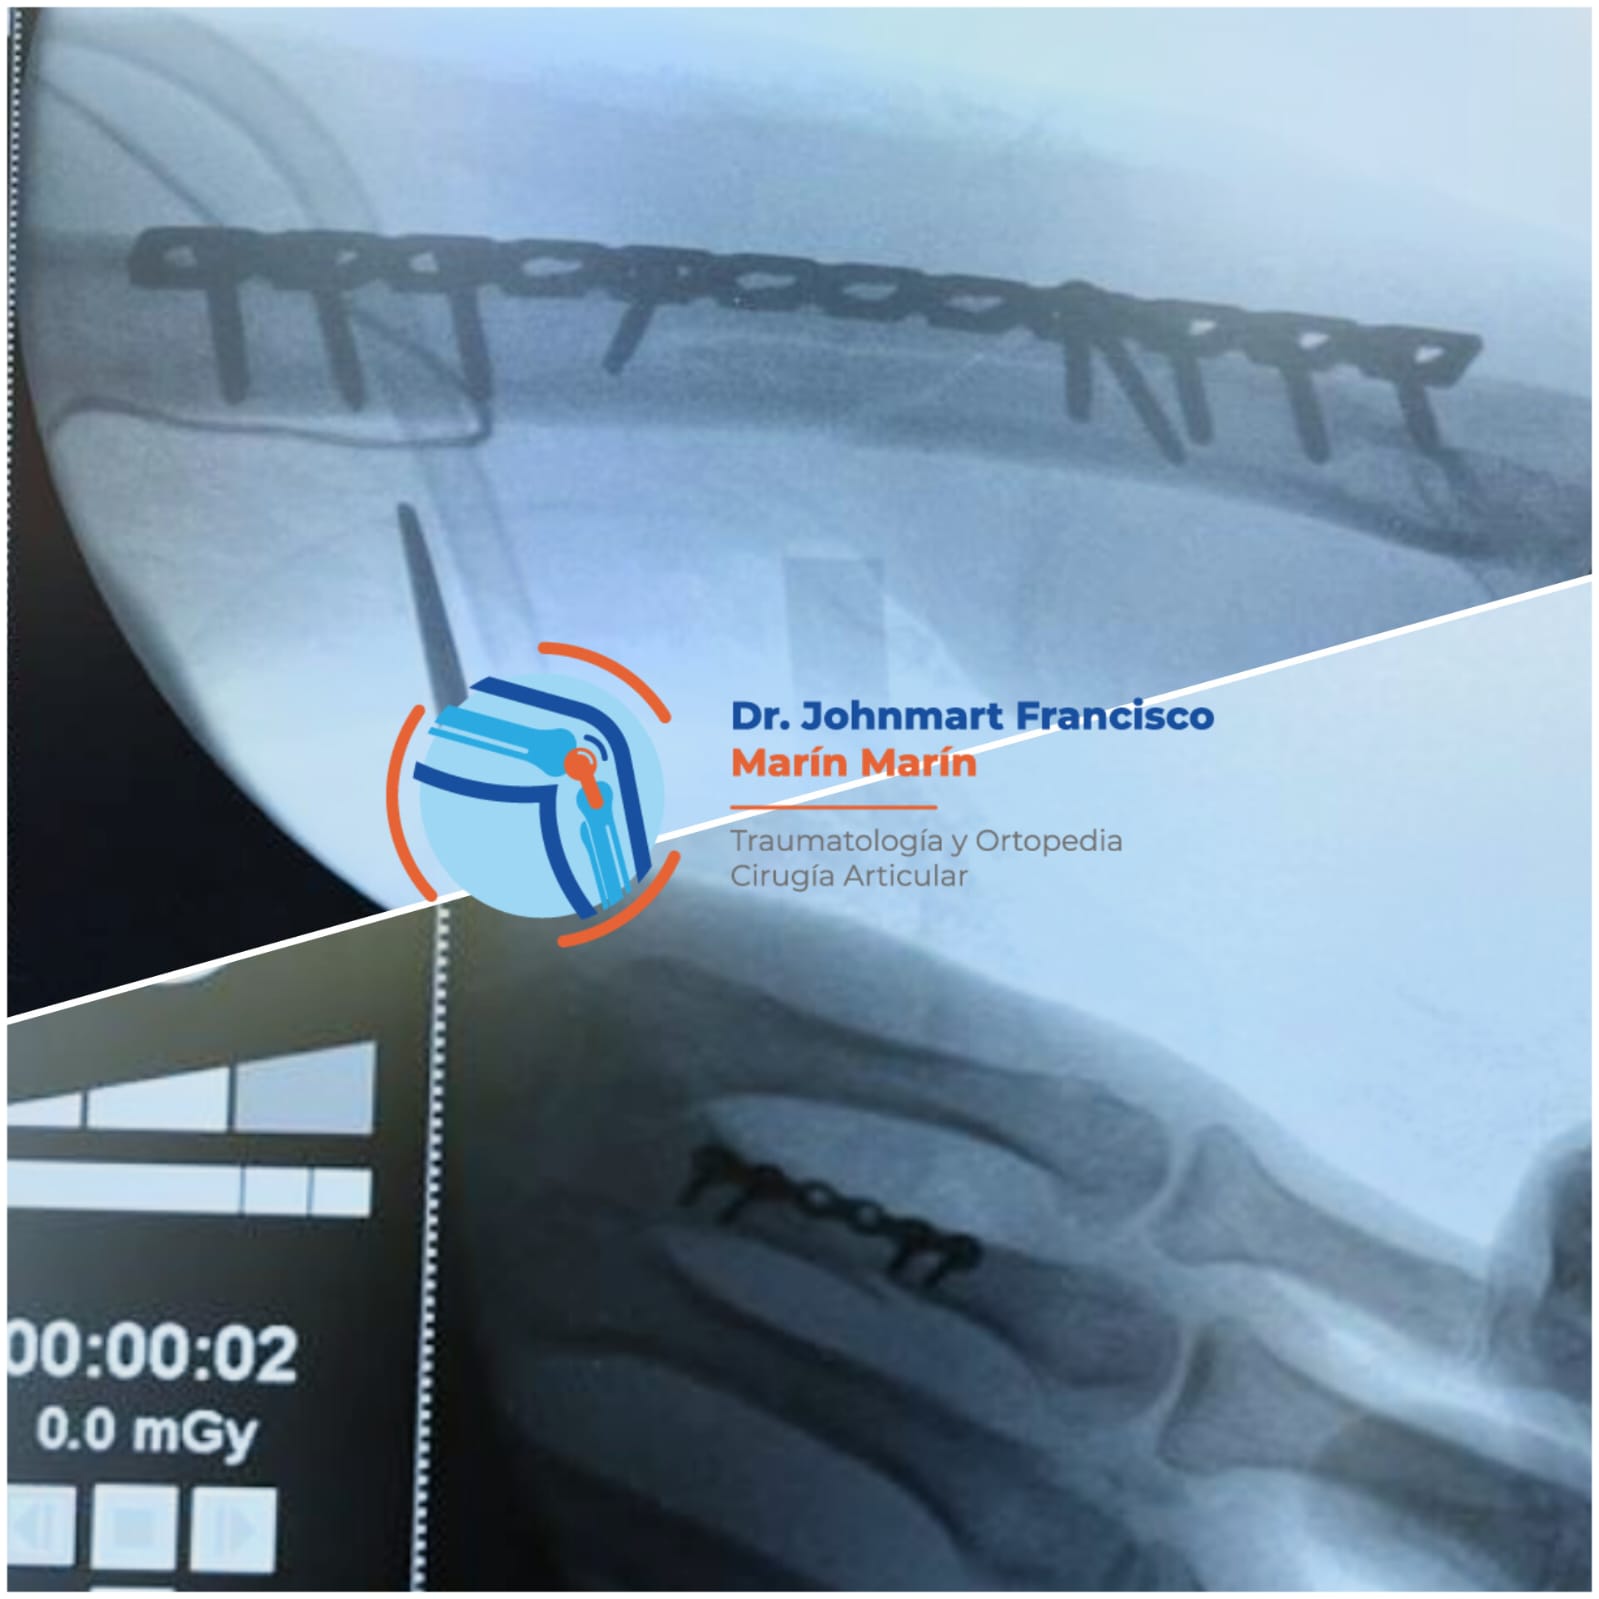

Atención a Lesiones

Lesiones Deportivas

Lesiones graves como fracturas, rupturas de ligamentos, esguinces o incluso luxaciones.